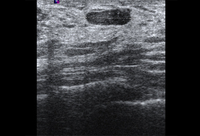

Ultrasonographic image of skin thickening in patient with inflammatory breast cancer

Courtesy of Dr Nancy Pile, University of Louisville; used with permission